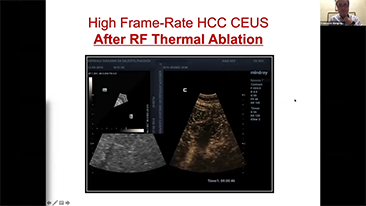

Solusi Pencitraan Umum Resona dari Mindray membantu para dokter mewujudkan diagnosis dan hasil pengobatan yang lebih akurat dan efisien melalui pemerik aplikasi subdivisi yang komprehensif dan alat bantu aplikasi klinis yang efisien.